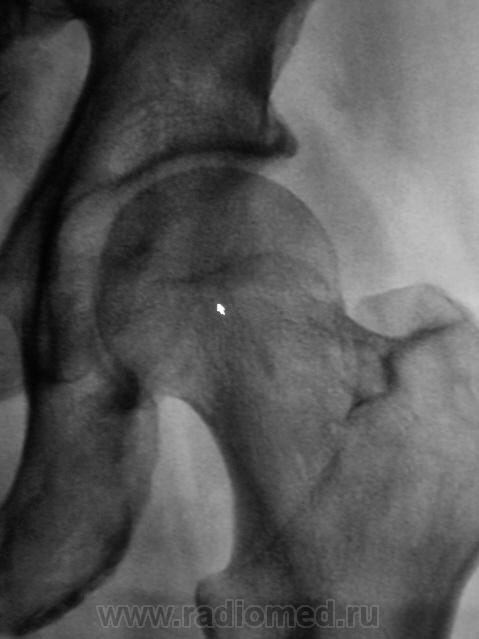

Следуюшая проекция.

!. Давайте попробуем, тогда объяснить тень на фоне головки бедренной кости, помеченную стрелками и выделенную в круг. Что это...?

Зона препараторного обызествления(с сопутствующей ей линией просветления)...т.е. - изменения по бывшей зоне роста...пациент то не особо и стар...

Нет, он еще не старик, ему 67 лет, но крепкий мужчина.

А как расценить линию, помеченную стрелочками?

То же самое, но по отношению к основанию большого вертела в условиях отведения...как мне кажется

Пациенту снимки в трех проекциях делались не за "просто так". Выставлю все рядышком.

Укладка практически идеальная, а головка, если внимательно присмотреться, не на месте. А невидимость линии уплотнения - это тоже один из сюрпризов шейки бедра. Хотя, искать ее надо на первых снимках, да и то не всегда увидишь. Через месяц искать нужно тонкую полоску разряжения.

А полоска разрежения видна.